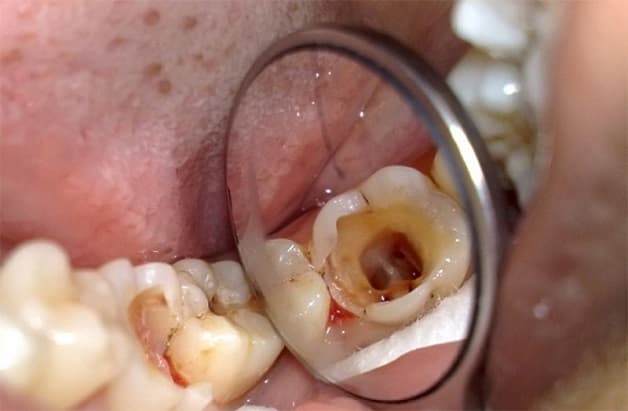

Sâu răng là hiện tượng tổn thương vĩnh viễn ở bề mặt răng, sâu răng phát triển trở thành những khe hở hoặc là lỗ nhỏ li ti trên bề mặt răng. Sâu răng hình thành do sự kết hợp của các yếu tố khác nhau dẫn đến hình thành vi khuẩn ở trong khoang miệng.

Nếu như sâu răng không được điều trị, tổn thương sẽ trở nên lớn dần đồng thời gây ảnh hưởng đến các phần sâu hơn của răng, điều này sẽ dẫn tới sâu răng nghiêm trọng, nhiễm trùng và thậm chí nặng nề hơn là nguy cơ mất răng.

– Sau khi men răng bị ăn mòn thành lỗ, vi khuẩn và thức ăn sẽ có điều kiện bám vào, acid sẽ được tạo ra nhiều hơn, tổ chức cứng

Sâu răng là hiện tượng tổn thương vĩnh viễn ở bề mặt răng